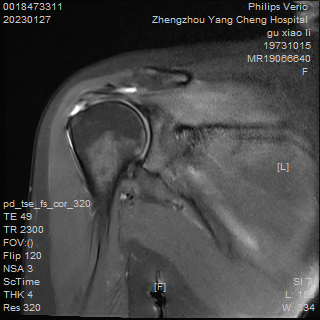

經(jīng)檢查診斷

右側(cè)肩袖損傷

損傷程度較嚴(yán)重

右肩部壓痛活動受限

右肩關(guān)節(jié)岡上肌肌腱全層斷裂

什么是肩袖損傷?

肩袖是由岡上肌、岡下肌、小圓肌和肩胛下肌四塊肌肉共同組成,它們的肌腱止于肱骨大、小結(jié)節(jié)把肩胛骨與肱骨相互連接,形狀相似于袖口把肱骨固定在盂窩,故名“肩袖”。肩袖損傷主要指組成肩袖的四塊肌肉的損傷,其中岡上肌最為常見。與多種因素相關(guān),包括年齡相關(guān)的退變、撞擊及創(chuàng)傷等。